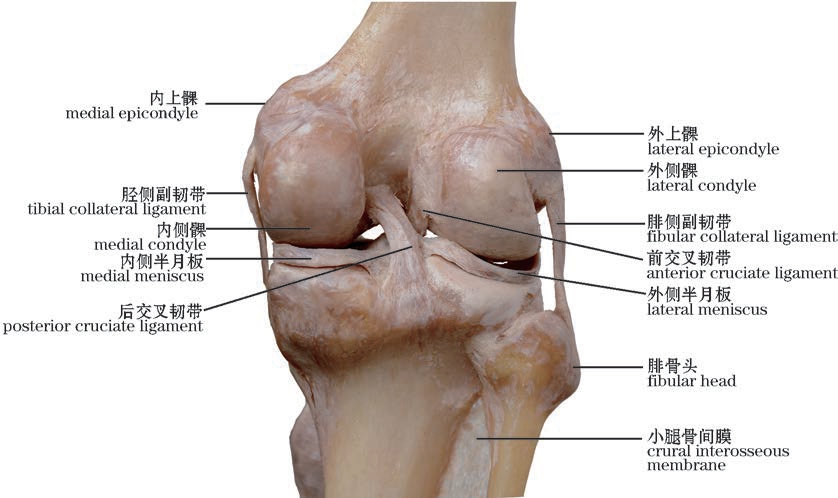

图2-42(1) 膝关节—1(前面观,右)

The knee joint—1(Anterior view,right)

img

图2-42(2) 膝关节—2(前面观,右)

The knee joint—2(Anterior view,right)